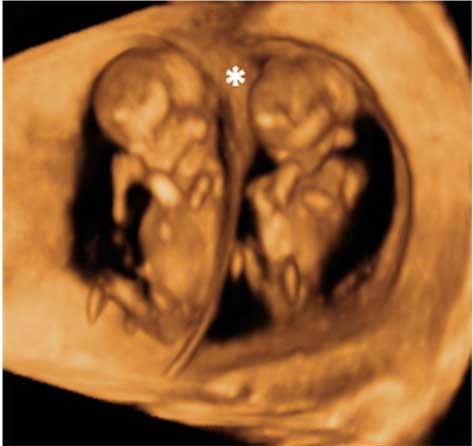

Ecografía 4D de la semana 12: Gemelos en bolsas diferentes

Esta ecografía en rotación muestra un embarazo gemelar de 12 semanas. La imagen en tres dimensiones muestra claramente dos fetos en sus respectivos sacos amnióticos. La membrana de separación entre ambas bolsas es bastante gruesa. Como la separación es muy clara, eso quiere decir que además de dos bolsas, existen dos placentas. Una de ellas se aprecia en la parte inferior izquierda de la cavidad uterina.

Ecografía 3D de gemelos de 12 semanas en bolsas diferentes